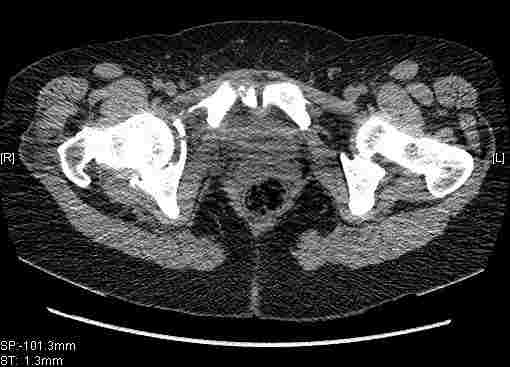

Удалось сегодня вывести пациентку в соседнюю больницу, где есть кт. Срезы сделаны только горизонтальные.

Следом 3d